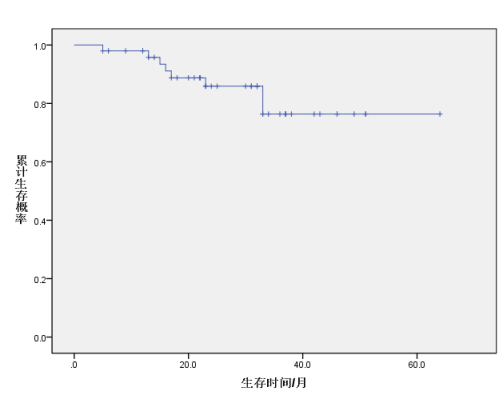

对50例未接受手术治疗脊索瘤患者进行生存分析,其随访时间(0~64)个月。使用K-M法进行生存分析,治疗结束时累计生存概率为1.0000,治疗结束后12、24、36个月的累计生存概率分别为0.9800、0.8590、0.7636。(见表1)

图1 治疗结束时到治疗结束后60个月生存曲线图